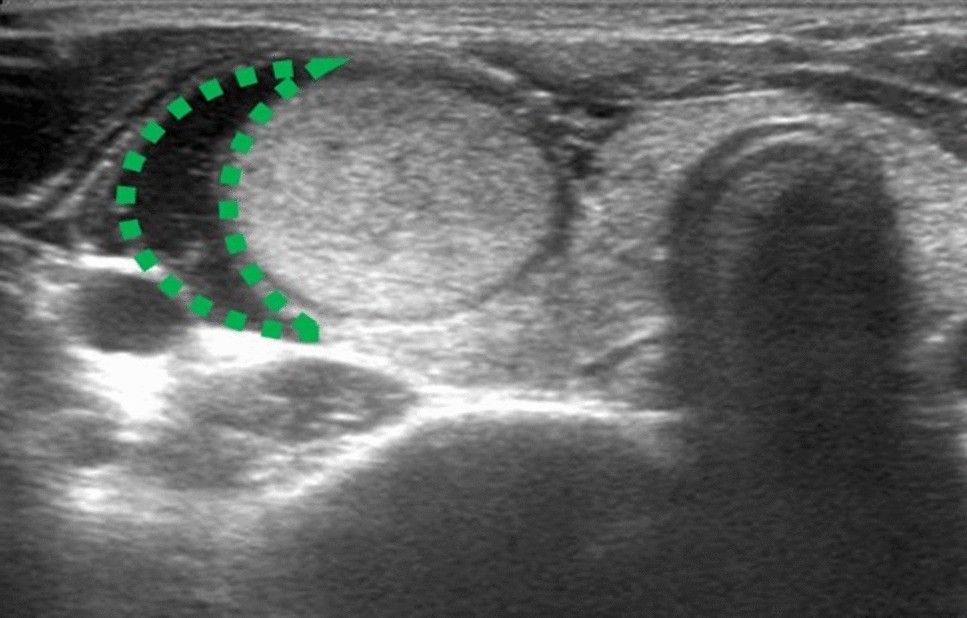

The hydrodissection with continuous fluid infusion. A buffering zone (green dotted line) was created to establish a liquid isolation zone > 0.5 cm in depth between the thyroid and adjacent structures.